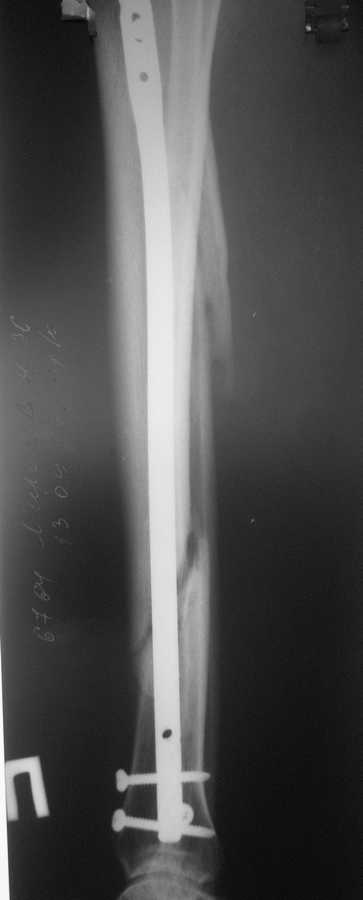

В январе 2009 года нами оперирована пациентка с переломом н\3 голени штифтом Expert. Динамизация через 4 месяца, пациентка при этом уже ходила с тростью. Дома периодически передвигалась без дополнительной опоры. В настоящее время - через 9 месяцев с момента операции периодически в вечернее время беспокоят ноющие боли в места перелома (не постоянно). При беседе выяснено, что боли чаще беспокоят после того, как днем она походит по дому без трости. Пальпаторно по гребню берцовой кости болей нет, но по задне-внутренней поверхности б\б кости пальпирутеся западение на уровне места перелома.В чем ошибка??? и что делать???

Недостаточная стабильность. Не использованы все возможности дистального запирания, нет самого проксимального из дистальных винтов. Два винта из трех коротковаты. В результате при диинамизации появился диастаз.

Тут есть уже опасность перелома стержня по ближайшему к перелому отверстию. Так что правильнее сделать реостеосинтез с рассверливанием. При введении гвоздя в дистальный отломок использовать отклоняющую спицу

или винт, чтобы стержень оказался не у переднего кортекса, как сейчас, а где и надо - посередине. Это обеспечит еще и встречно-боковую компрессию.

Значит, изначально в периферическом отломке гвоздь шел не по центру, а ближе к передней стенке. Это не очень хорошо.

Да, динамизация поздновата. Да дистальный отломок заперт одним винтом, два другие короткие, еще дно отверстие пустое...

Этот 9-ти мм. стержень ExpertTN вряд ли скоро сломается, если, конечно же, пациентка не имеет большого веса (>100 kg). Перештифтовать более толстым штифтом с рассверливанием, пожалуй, самый надежный вариант, но не факт, что единственный. Вполне правомочно подумать просто о косой остеотомии малоберцоыой кости (зачем резекция???) в средней 1/3 и попытке дополнительной стабилизации дистального отломка путем запирания штифта через свободное отверстие (наиболее проксимальное из дистальных) и замены двух самых дистальных винтов, причем косой самый дистальный лучше провести в другой плоскости. Возможно этого будет вполне достаточно для сращения...а вот периодически возникающие боли могут и остаться(((

По снимку гвоздь сидит плотно в узкой части большеберцовой, а на периферии нестабильная блокировка. Динамизация работает в течение первых 8 недель.

А так по давности (9 мес) уже сформировался ложный сустав и трудно рассчитывать на сращение без замены гвоздя. Общепринятая тактика, обычный реостеосинтез с рассверливанием даст хороший результат, потому что рассверливание канала стимулирует процесс при ложных суставах и более массивный гвоздь создаст нужную стабильность.